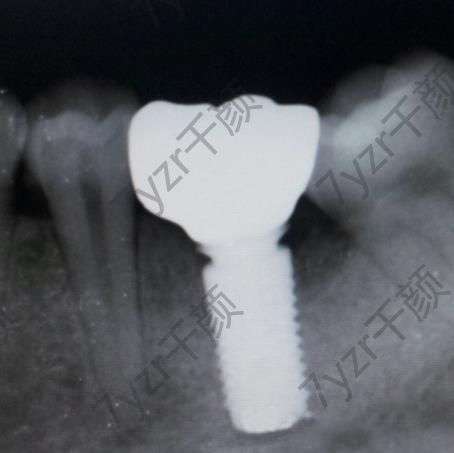

時間過得實在是太快了。我感覺這三個月要比我想象中過得快一些,也有可能是因為這一段時間工作比較忙的原因吧。沒有時間去瞎想,所以感覺時間就過的更快了,現(xiàn)在的我已經(jīng)裝上牙冠了??傮w來說,這種感覺還是挺不錯的,畢竟已經(jīng)沒有了那個牙洞。現(xiàn)在的我因為剛剛裝上牙冠沒有多長時間,所以現(xiàn)在還在忌口,醫(yī)生說再堅持一段時間就什么東西都可以吃了。

因為我種植牙到這件事情沒有告訴我的媽媽。前幾天放假回家的時候,我還特意張開嘴巴讓我他看我嘴巴里有什么變化。媽媽一眼就看出來,我之前的那個牙洞沒有了,還問我那個地方裝的是什么東西,我告訴她是一顆新的牙齒,媽媽還特別的疑問說,這么大了,怎么可能長出新的牙齒?我告訴他,我是去口腔醫(yī)院種植的牙齒,媽媽還特意觀察了一下,不仔細看的話,根本看不出來是假的。